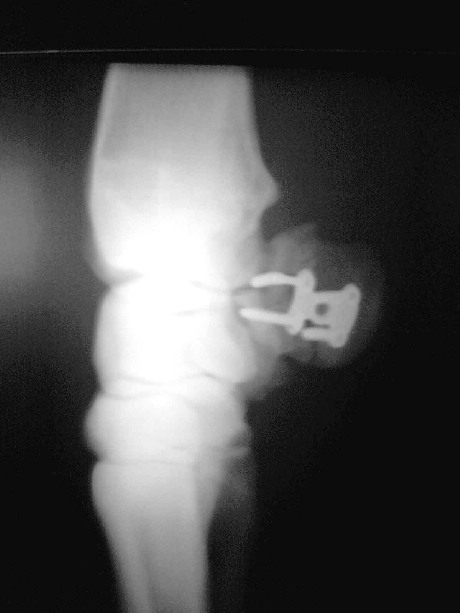

Griffelbeinfraktur

Entfernung der Splitter und Stabilisierung des Gelenksbeteiligten

Teiles mit Zugschraube